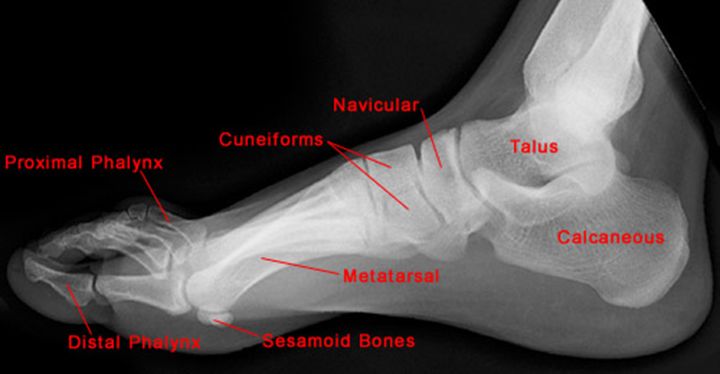

正常足侧位片

正常足正位片

跟骨骨折

Jones Fracture

第五跖骨基底部骨折

易漏诊

不制动易致骨不连

跖骨骨折